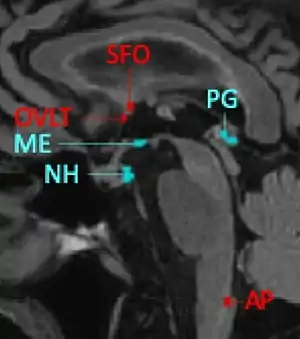

Ubicación de los NHO/CVO en el cerebro humano.Imagen sagital de RMN. En rojo los CVO sensoriales; en azul los secretores. * NH: neurohipófisis * AP: área postrema. * ME:Eminencia media. * PG:Glándula pineal * SFO:Órgano subfortcial. *OVLT:Órgano vasculoso de la lamina terminalis.[1]

En 2021 se listaban como órganos neurohemáticos circunventriculares (NHO/CVO) a los siguientes: órgano vasculoso de la lámina terminal (OVLT), órgano subfornical (SFO), neurohipófisis (NHip), eminencia media (ME), órgano subcomisural (SCO), glándula pineal (PG), área postrema (AP). A estos se suma el Plexo coroideo (CP) que presenta caracteres similares.[9]